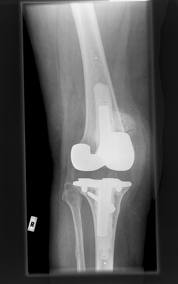

Medical technology m

arches on, with new designs for artificial hips and knees, but the hips and knees themselves march no better than older models. Which is bad news, because those older models have been marching so poorly that they are expected to fail much sooner than the 15 years that most patients were promised. The New York Times reports that a study of 1oo hip replacements using new models made between 2003 and 2007 found that “not a single new artificial hip or knee introduced over a recent five-year period was any more durable than older ones. In fact, 30 percent of them fared worse.” Yikes! The bad news gets worse when one considers that about 700,000 Americans will have hips or knees replaced this year. Read more in the New York Times.